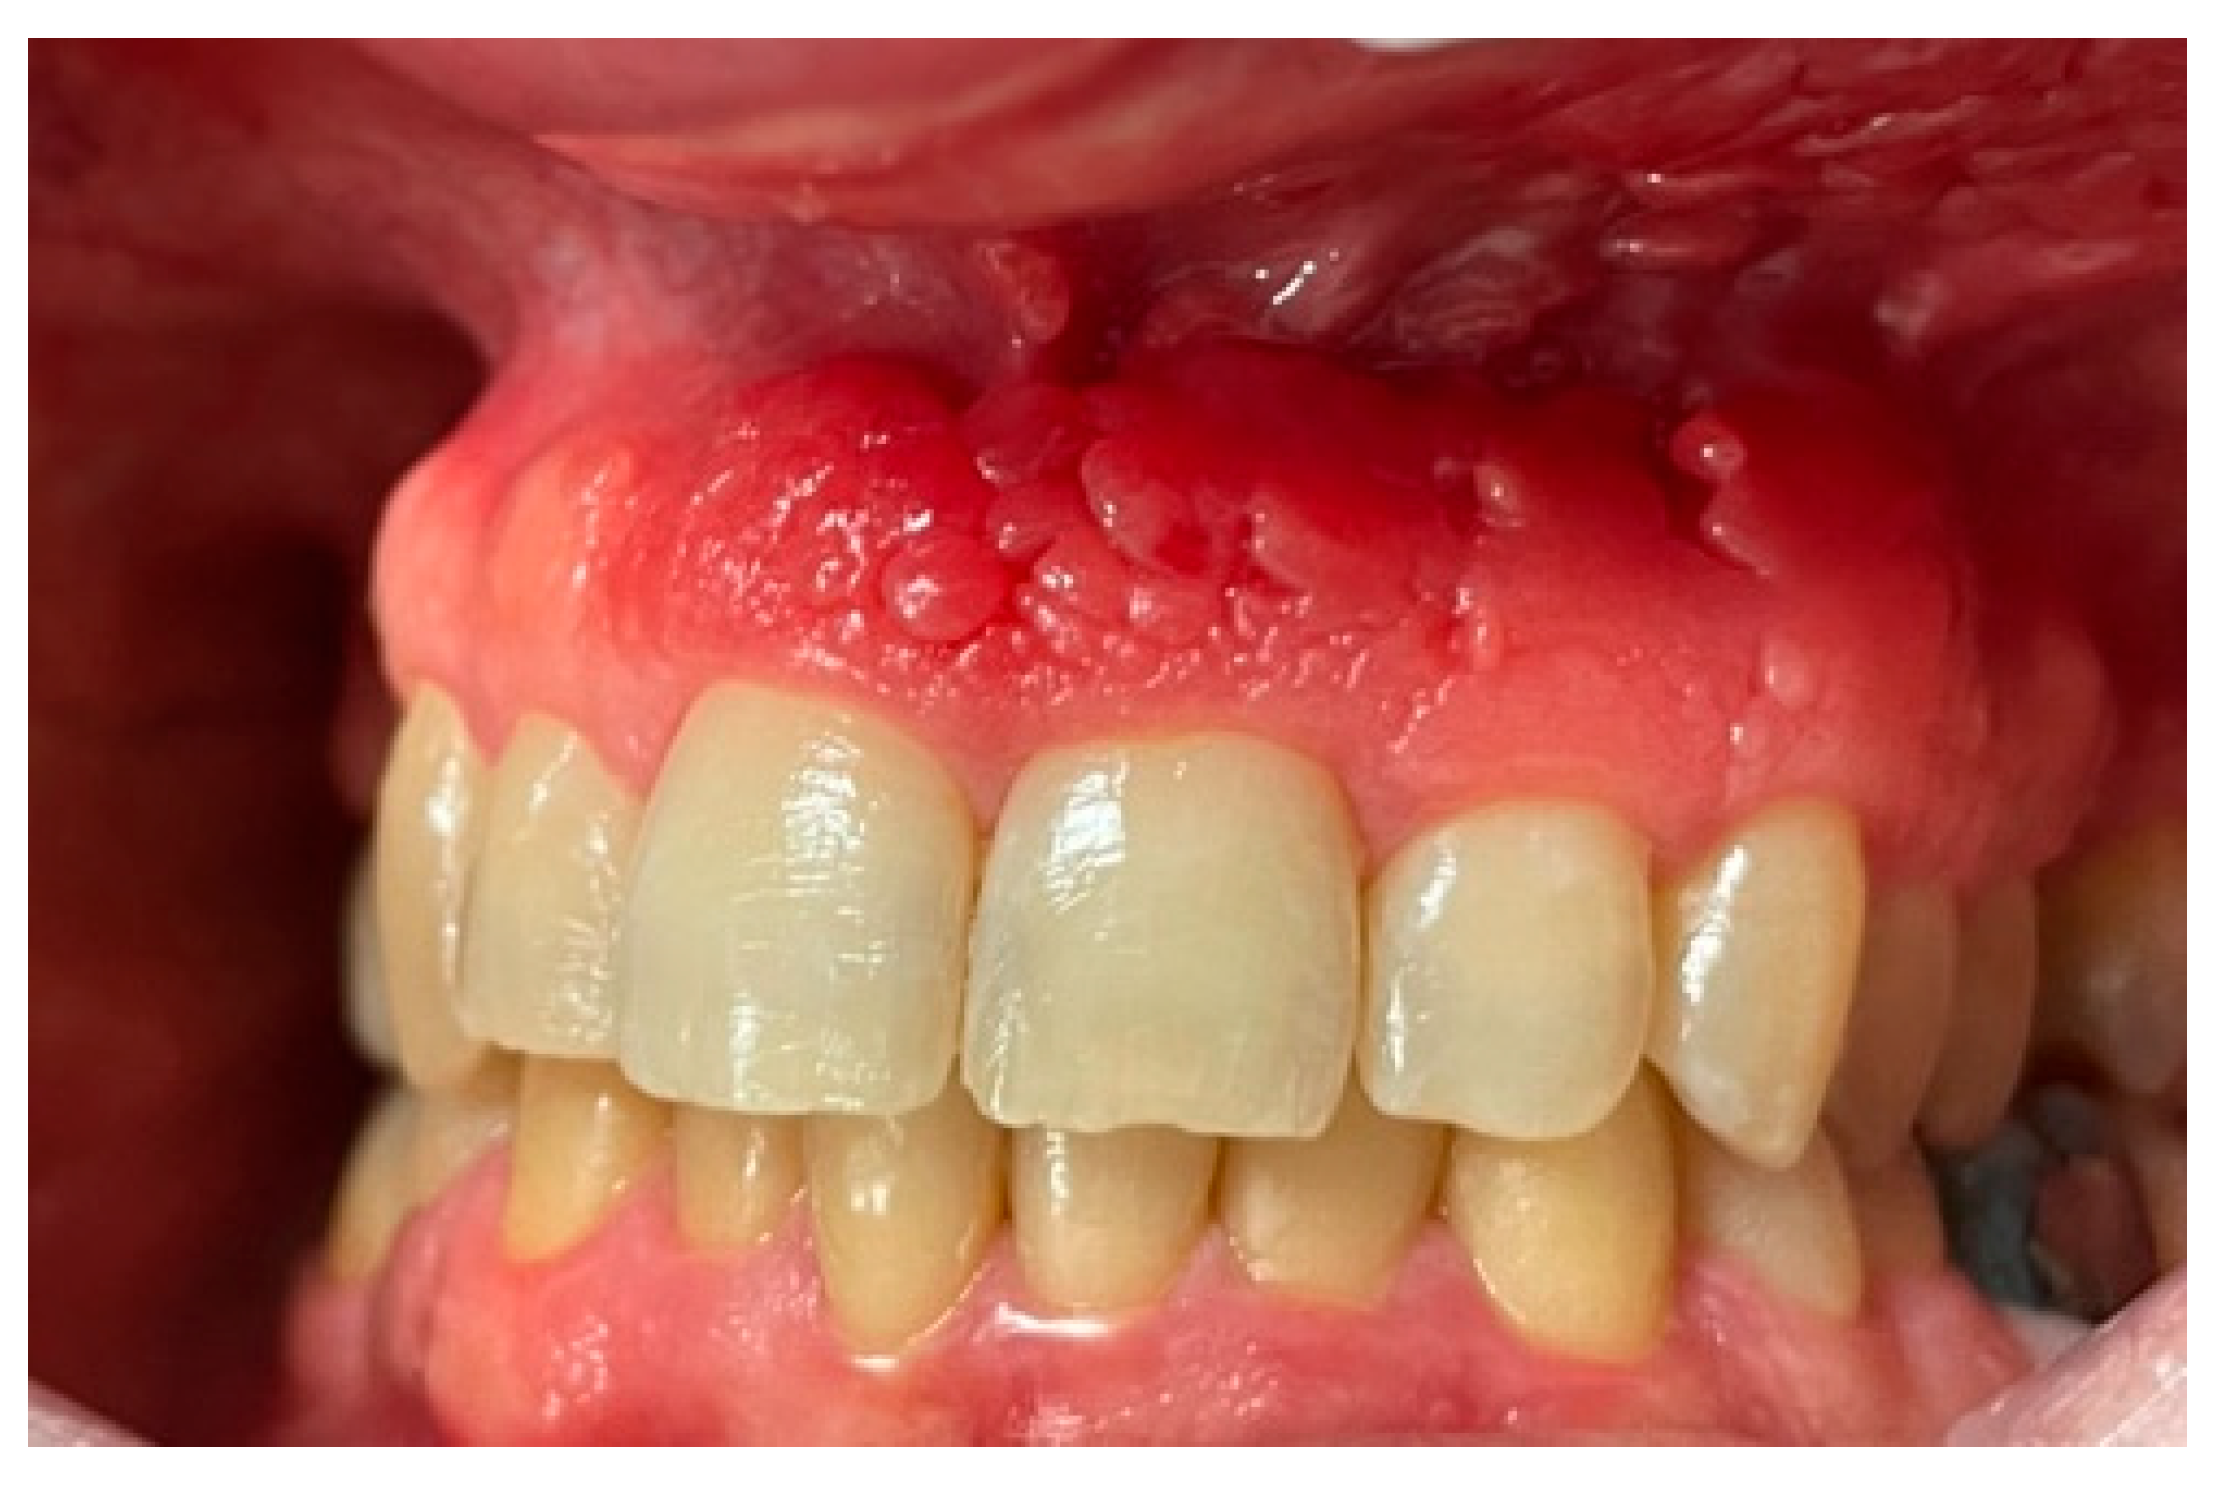

Intraoral examination revealed an erythematous and edematous lesion in the maxillary region, extending from the upper right central incisor to the upper left canine, involving the adjacent alveolar mucosa. The gingiva appeared polypoid and bled upon probing. The gingival tissues in the adjacent areas were clinically healthy, with only mild inflammation, likely secondary to suboptimal oral hygiene (Figure 1 and Figure 2).

Figure 1. Clinical presentation of the lesion at the first clinical assessment: polypoid, erythematous, and edematous gingival tissue localized in the anterior maxillary region, with spontaneous bleeding upon probing.

Diagnosis of PCG was based on intraoral findings characterized by an erythematous gingiva with loss of stippling [14]. First oral examinations performed and described by Leuci et al. [1] allowed clinicians to detect lesion characteristics in 40 out of 45 cases, specifying the predominant clinical phenotype or provisional diagnosis for each. Among these groups, 25 cases (62.5%) were identified as bullous or nonspecific blistering mucositis, 4 cases (10%) were classified as erythematous lesions consistent with erythroplakia, 4 cases (10%) as keratotic lesions resembling oral lichenoid conditions, 4 cases (10%) as verruciform lesions with features suggestive of malignancy, and 3 cases (7.5%) as ulcerative lesions of indeterminate etiology [1]. In this case report, the lesion appeared polypoid, erythematous, and edematous at the baseline.